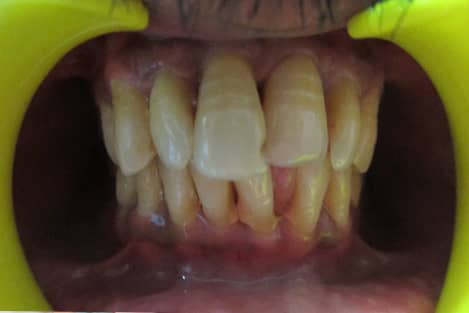

Non Vital Tooth Bleaching